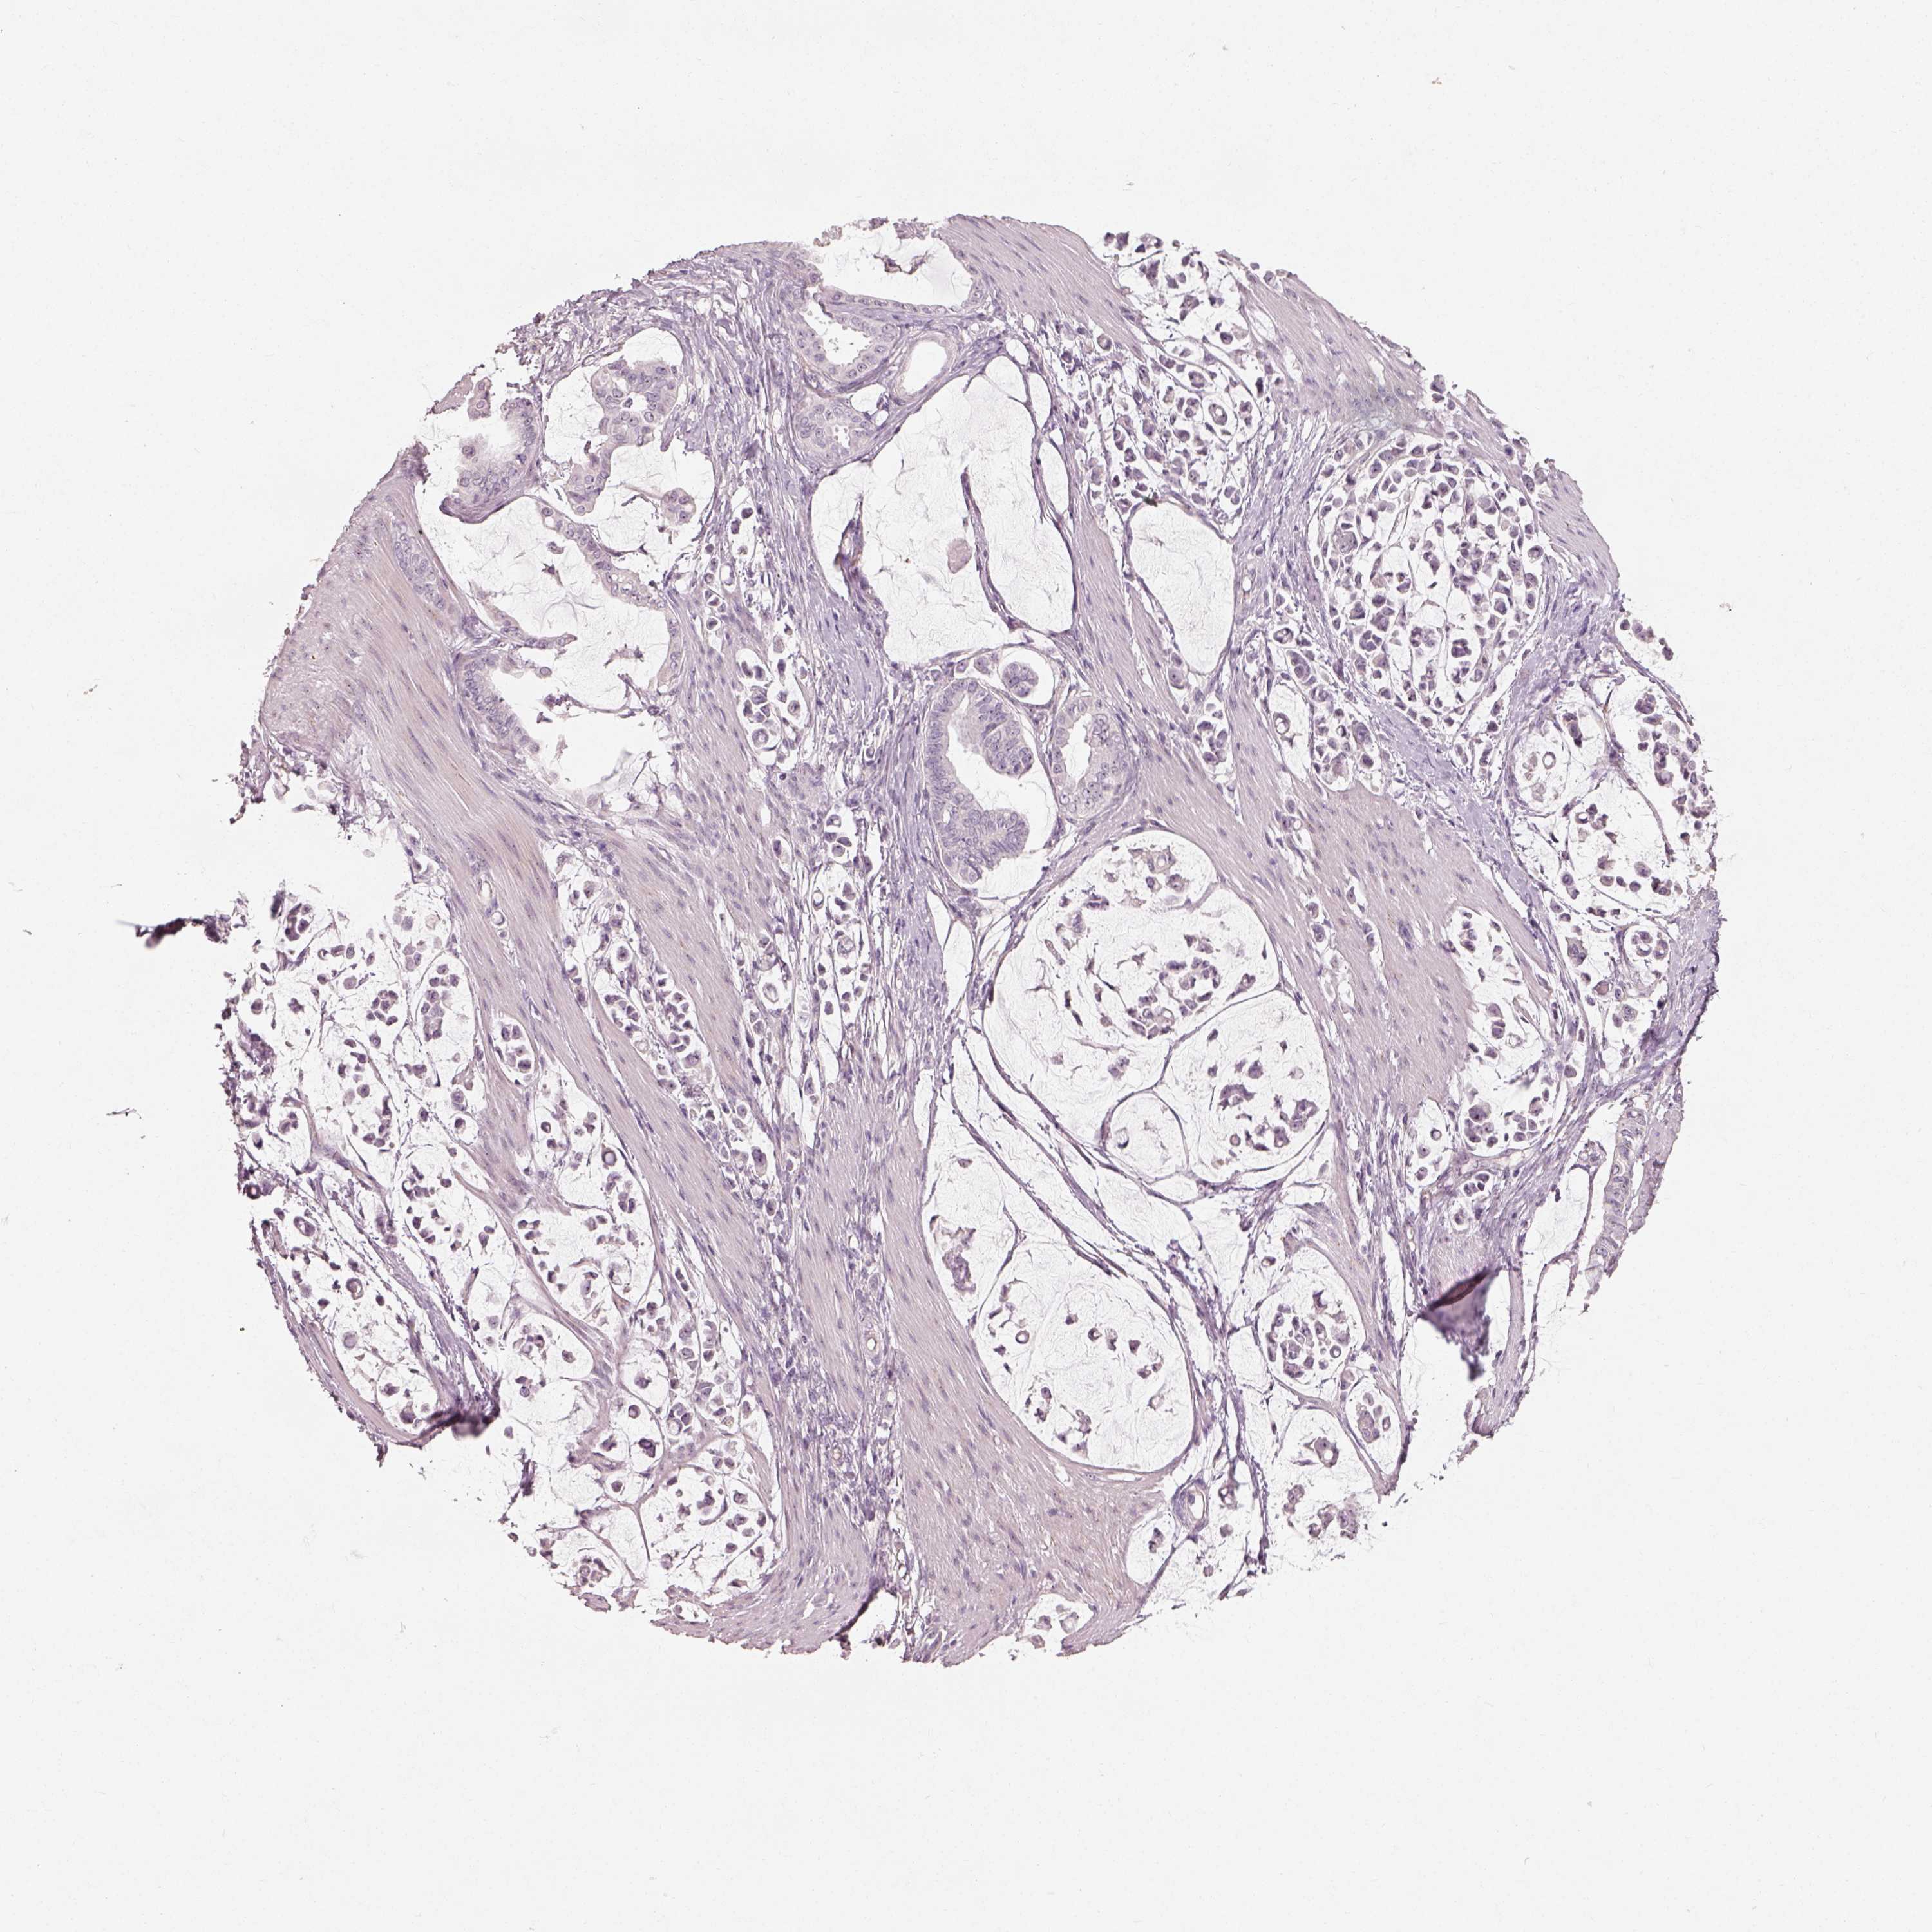

STOMACH CANCER - Protein expressioni

A mouse-over function shows sample information and annotation data. Click on an image to view it in a full screen mode. Samples can be filtered based on level of antibody staining by selecting one or several of the following categories: high, medium, low and not detected. The assay and annotation is described here.

Antibody stainingi

Antibody staining in the annotated cell types in the current human tissue is reported as not detected, low, medium, or high, based on conventional immunohistochemistry profiling in selected tissues. This score is based on the combination of the staining intensity and fraction of stained cells.

Each image is clickable and will lead to virtual microscopy that enables deeper exploration of all samples and also displays staining intensity scores, fraction scores and subcellular localization as well as patient and tissue information for each sample.

Antibody HPA036187

Antibody HPA064546

Staining

High

Medium

Low

Not detected

Intensity

Strong

Moderate

Weak

Negative

Quantity

>75%

75%-25%

<25%

None

Location

Nuclear

Cytoplasmic/membranous

Cytoplasmic/membranous,nuclear

Adenocarcinoma, NOS